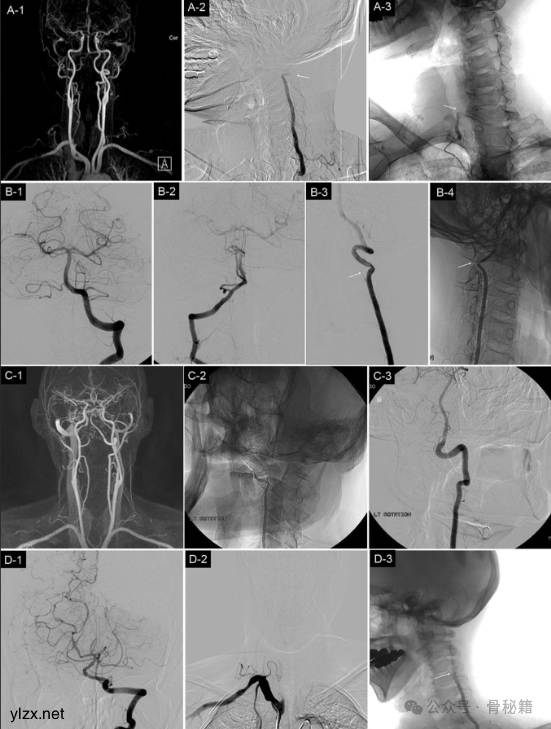

- 磁共振血管造影(MRA)

:用于评估椎动脉及椎基底动脉系统的血流情况。

- 椎动脉造影

:直接观察椎动脉形态及血流动力学变化。

- 旋转椎动脉型眩晕(弓猎人综合征)

:多见于老年患者,头部转动时椎动脉受压,引起椎基底动脉供血不足,诱发眩晕。

- 手术治疗

:对于保守治疗无效的 Barré - Liéou 综合征或旋转椎动脉型眩晕患者,可考虑手术干预,如经皮激光椎间盘减压术、前路颈椎融合术或椎动脉减压术等。但需严格评估手术适应证,对于存在对侧椎动脉闭塞或发育不良的患者,应谨慎选择手术治疗。